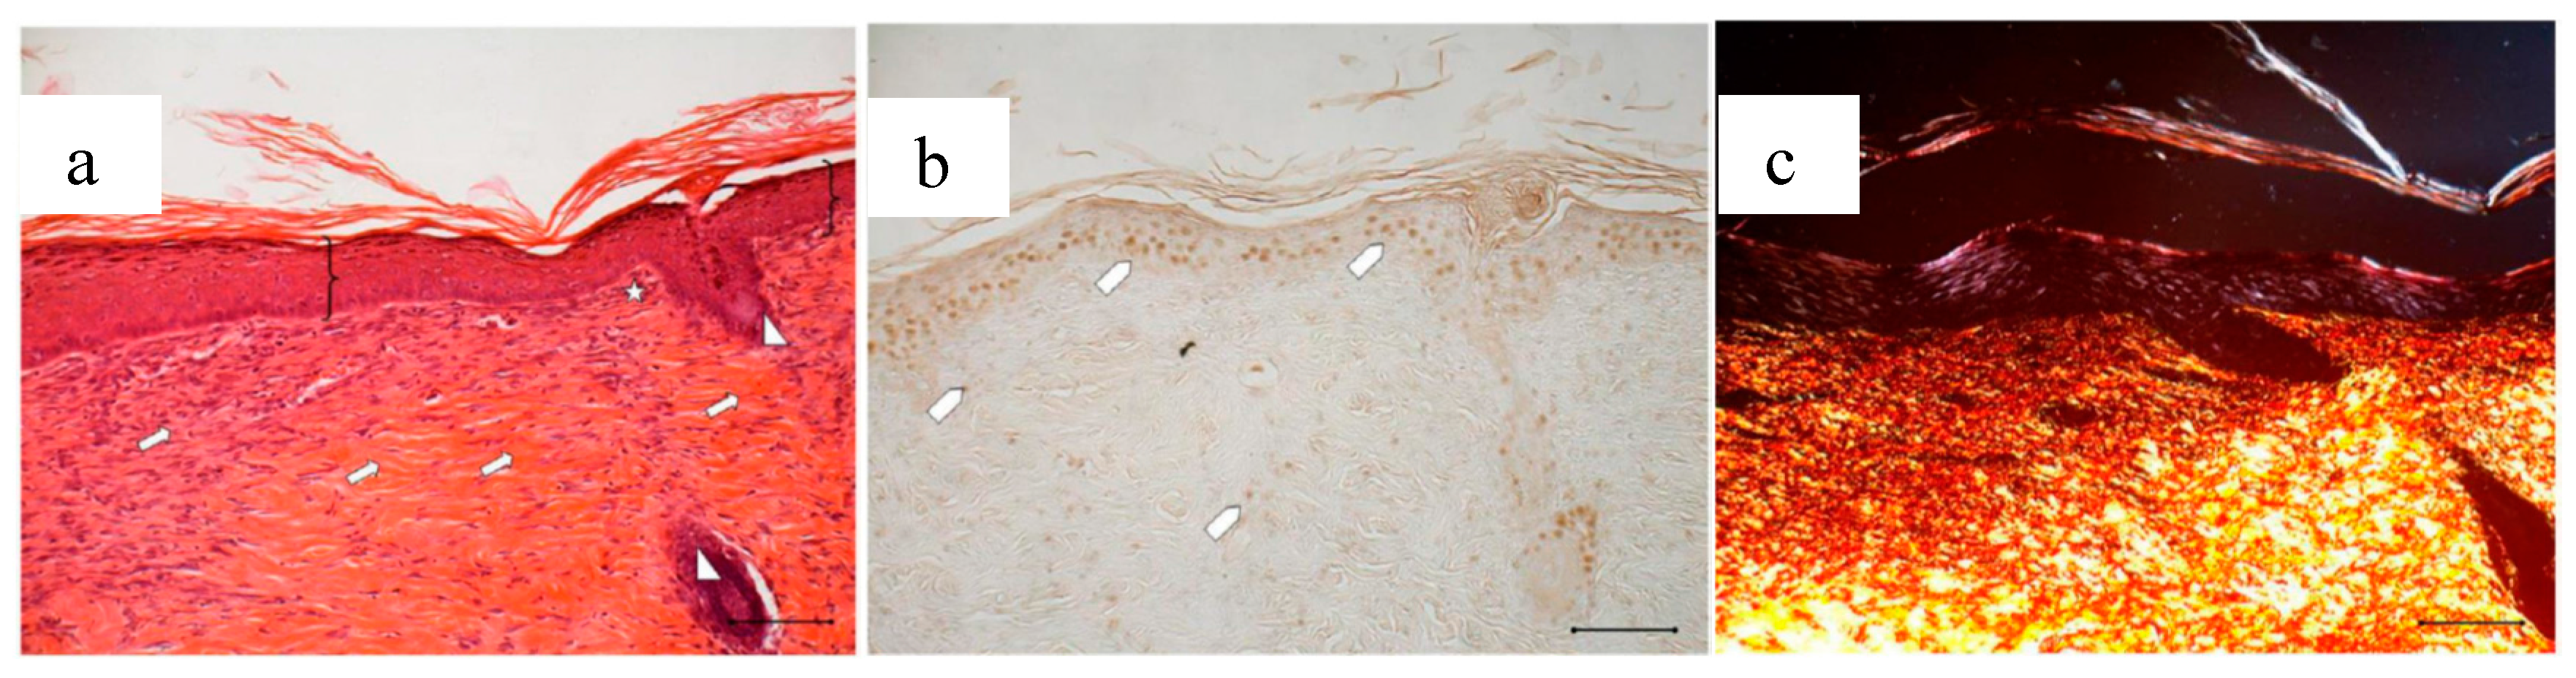

Figure 15.

Treatment with 4 mg bioactive dressing (BD-4 mg) for 18 days. Representative images of skin slice sections stained: (a) with H&E; (b) with BrdU; and (c) with red picrosiurius after treatment with. Scale bar: 200 µm.

Wounds treated with 4 mg bioactive dressing (BD-4 mg) after 18 days are completely re-epithelized, epidermis (bracket) is well organized in multiple layers of cells, and has a fair degree of keratinization. Even in the very middle of the scar, dermal papillae (white star) are developing, as well as dermal appendages (white triangle).

In anti-BrdU reaction, the number of proliferating cells (white pentagon) is similar to that of a mature skin. Picrosirius red-staining shows that dermal collagen appears to be rich in Green/Yellow fibers (mainly collagen III). Increasing the weight of BD applied to the wound seems therefore to improve its reparative effect, which results faster and more complete after treatment with BD-4 mg, compared to treatment with BD-2 mg.